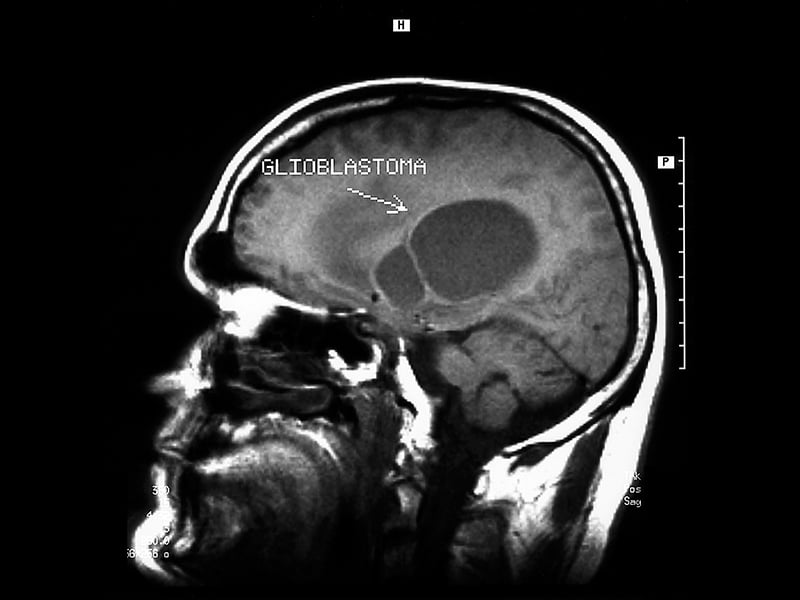

During a magnetic resonance imaging scan, atoms in the patient's body are exposed to a strong magnetic field. The technologist applies a radiofrequency pulse to the field, which knocks the atoms out of alignment. When the technologist turns off the pulse, the atoms return to their original position. In the process, they give off signals that are measured by a computer and processed to create detailed images of the patient's anatomy. Medical radiation isn't used in MR procedures.

Magnetic resonance image of head / Image © ASRT

Magnetic resonance image of head

Image © ASRT